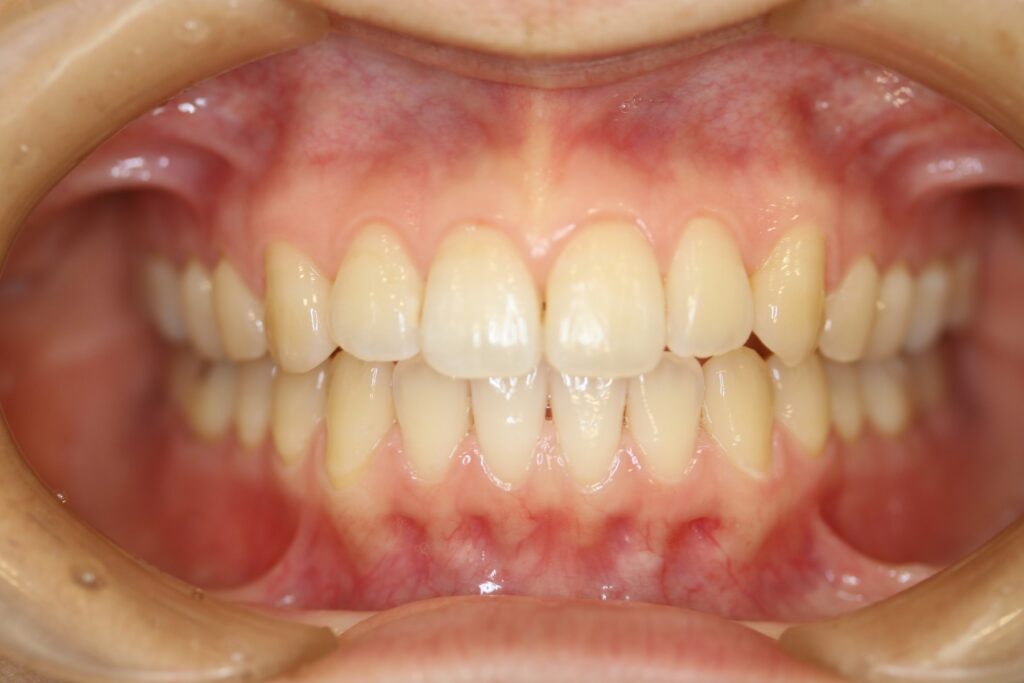

治療実績(症例) アライナー矯正 症例1 上顎前突症例 症例2 上下顎前突症例 症例3 叢生 症例4 開咬 症例5 開咬(外科的矯正治療) アライナー矯正 Post Share Hatena Line RSS feedly Pin it note 1.主訴2.診断名3.初診時年齢4.治療に用いた主な装置とオプション5.抜歯部位6.治療期間・通院回数7.総額と費用内訳総額相談検査・診断料調整料4,000円8.リスク・副作用 治療前 治療中 治療後